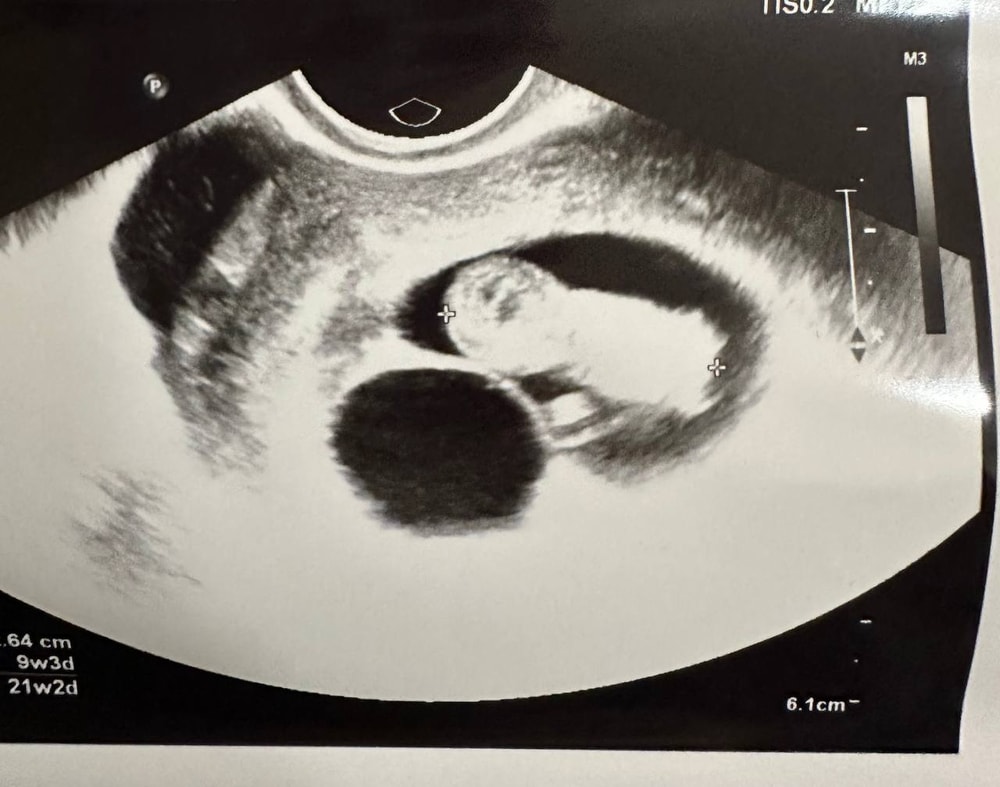

Эмбрион приживается, Иду на узи, а там 2 плодных яйца. Именно 2 отдельно.

Вот, собственно, узи на 9й неделе.

Второе ПЯ было с анэмбрионией.